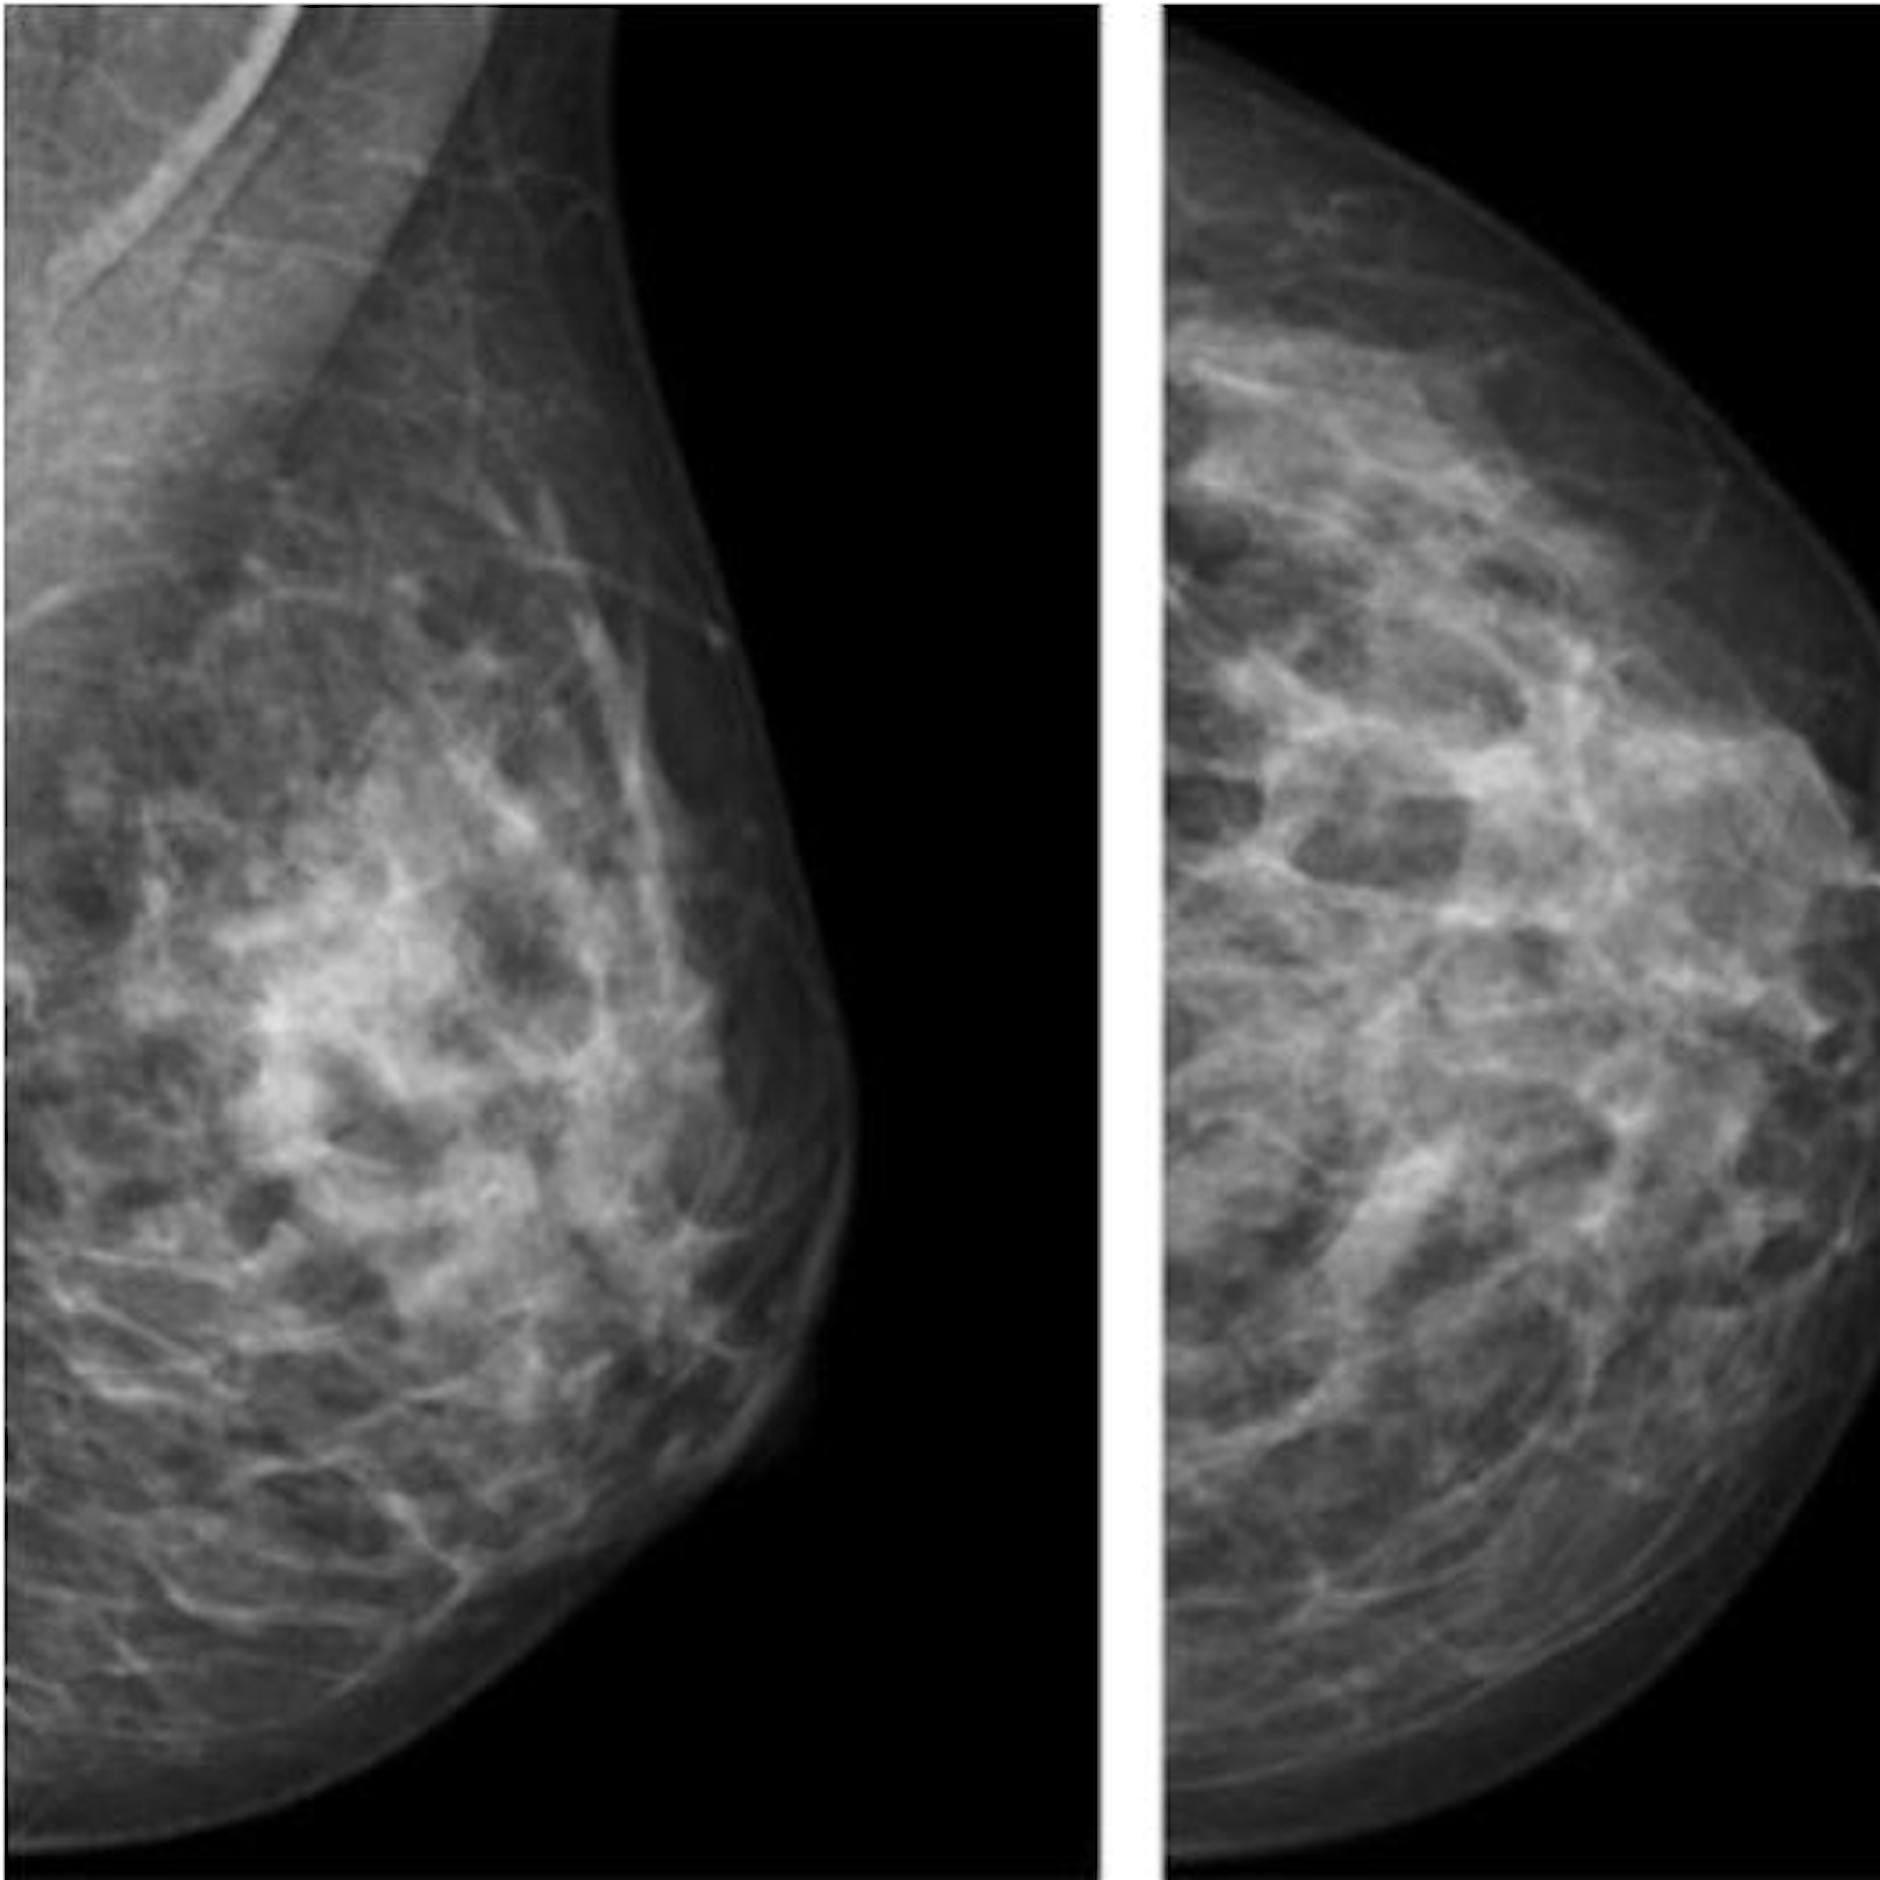

Viele bei einer Chemotherapie eingesetzten Medikamente, aber auch die Strahlen einer Strahlentherapie, wirken besonders auf schnell wachsende und sich häufig teilende Zellen. Dazu zählen Tumorzellen, aber auch Haarwurzelzellen, die sich in der Wachstumsphase befinden. Sind die Haarwurzeln geschädigt, fallen die Haare aus oder brechen über der Wurzel ab. Genau hier setzt die Kopfhautkühlung an.